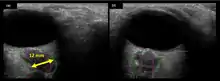

The astronauts affected by long term visual changes and prolonged intracranial hypertension have all been male, and SOS may explain this because in men, the sternocleidomastoid muscle is typically thicker than in women and may contribute to more compression. The reason that SOS does not occur in all individuals may be related to anatomic variations in the internal jugular vein. Ultrasound study has shown that in some individuals, the internal jugular vein is located in a more lateral position to Zone I compression, and therefore not as much compression will occur, allowing continued blood flow.

Intracranial pressure (ICP) needs to be directly measured before and after long duration flights to determine if microgravity causes the increased ICP. On the ground, lumbar puncture is the standard method of measuring cerebral spinal fluid pressure and ICP,[6][44] but this carries additional risk in-flight.[4] NASA is determining how to correlate ground-based MRI with inflight ultrasound[4] and other methods of measuring ICP in space is currently being investigated.[44]

There are different approaches to non-invasive intracranial pressure measurement, which include ultrasound "time-of-flight" techniques, transcranial Doppler, methods based on acoustic properties of the cranial bones, EEG, MRI, tympanic membrane displacement, oto-acoustic emission, ophthalmodynamometry, ultrasound measurements of optic nerve sheath diameter, and Two-Depth Transorbital Doppler. Most of the approaches are "correlation based". Such approaches can not measure an absolute ICP value in mmHg or other pressure units because of the need for individual patient specific calibration. Calibration needs non-invasive "gold standard" ICP meter which does not exists. Non-invasive absolute intracranial pressure value meter, based on ultrasonic Two-Depth Transorbital Doppler technology, has been shown to be accurate and precise in clinical settings and prospective clinical studies. Analysis of the 171 simultaneous paired recordings of non-invasive ICP and the "gold standard" invasive CSF pressure on 110 neurological patients and TBI patients showed good accuracy for the non-invasive method as indicated by the low mean systematic error (0.12 mmHg; confidence level (CL) = 0.98). The method also showed high precision as indicated by the low standard deviation (SD) of the random errors (SD = 2.19 mmHg; CL = 0.98).[46] This measurement method and technique (the only non-invasive ICP measurement technique which already received EU CE Mark approval) eliminates the main limiting problem of all other non-successful "correlation based" approaches to non-invasive ICP absolute value measurement – the need of calibration to the individual patient.[47]